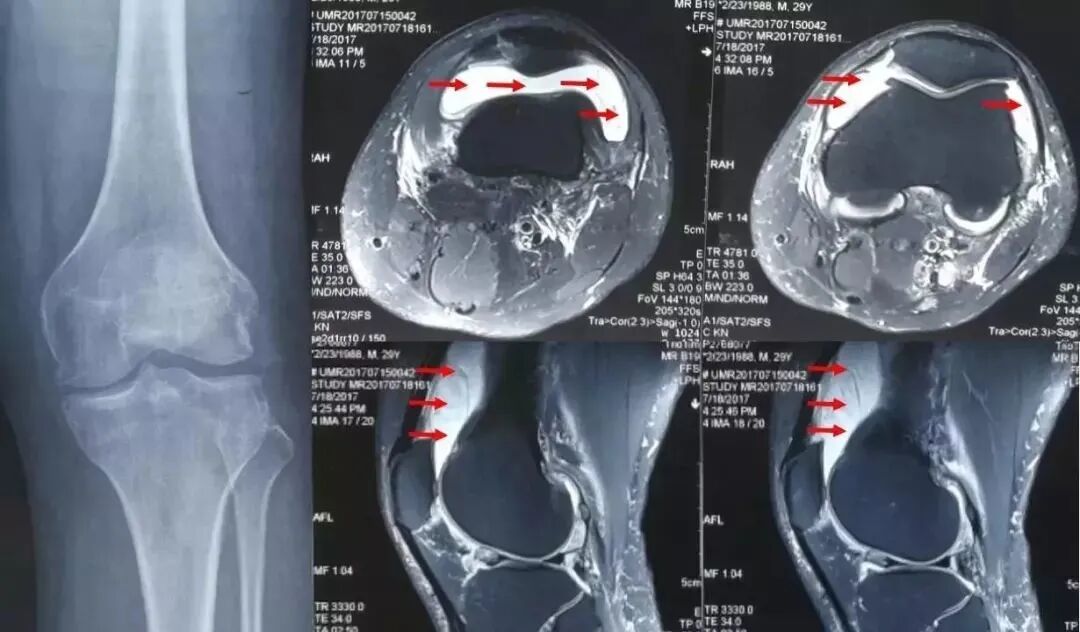

如有必要,可能需要进行关节MRI检查,只有MRI才能清晰的看到滑膜组织,并且可以清楚地看到关节腔内液体。

核磁共振检查可清楚显示膝关节腔积液,滑膜增厚(红色箭头指示)